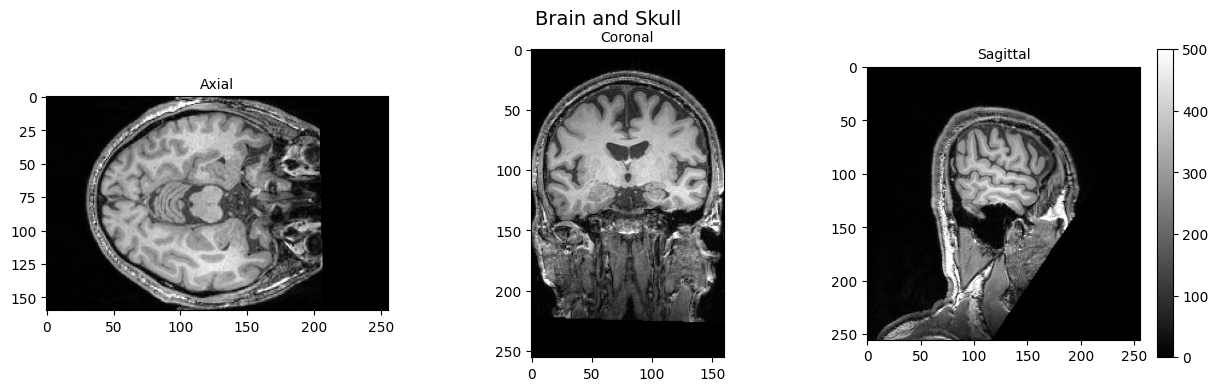

│ ├── sub-002_ses-01_task-cmrr2p5isomb3me3TR1500_dir-AP_echo-3_bold.nii.gz

│ ├── sub-002_ses-01_task-cmrr2p5isomb3me3TR1500_dir-AP_echo-3_sbref.json

│ └── sub-002_ses-01_task-cmrr2p5isomb3me3TR1500_dir-AP_echo-3_sbref.nii.gz

└── sub-002_ses-01_scans.tsv

12 directories, 72 files

pyBIDS#